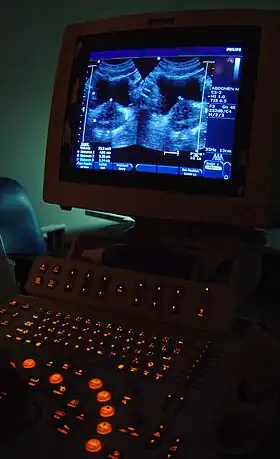

Componentes del ecógrafo

El sistema de procesamiento

Es la propia máquina de la ecografía donde tiene lugar el procesamiento de la información obtenida mediante los ultrasonidos, consta de tres partes:[21]

- CPU o unidad de procesamiento central: Es básicamente un ordenador con procesador y placa base.[21]

- Sistema de almacenamiento: Los ecógrafos generan imágenes y datos los cuales requieren almacenamiento para su estudio, por esta razón cuentan con importantes cantidades de memoria.[21]

- Consola: Para poder manejar los diferentes parámetros de la ecografía e introducir datos, realizar mediciones y otros aspectos el aparato consta de un teclado, ratón , ruedas y palancas.[21]

- Monitor: Es la pantalla donde se visualizan las imágenes ecográficas, datos del paciente y el resto de la información.[21]